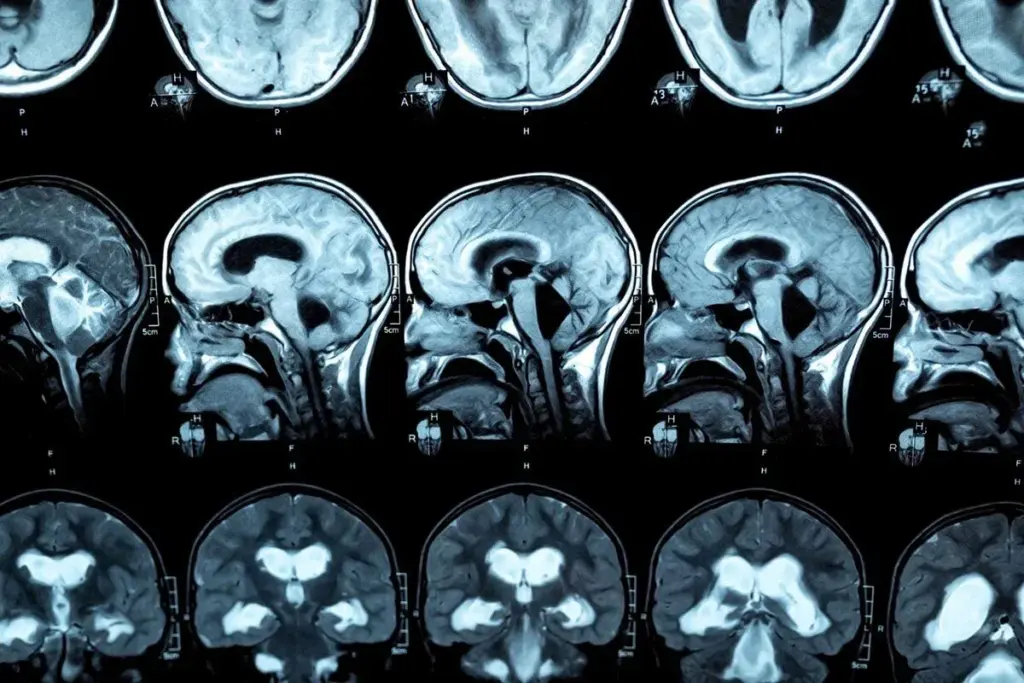

Neuroimaging Studies of Brain Ventricles

Neuroimaging is key in diagnosing hydrocephalus. We use ultrasound, CT, and MRI to see the brain’s ventricles. This helps us check their size and shape.

Ultrasound is great for infants because it’s safe and doesn’t use radiation. It can spot enlarged ventricles, a sign of hydrocephalus.

CT scans give detailed brain images and can quickly spot ventricular enlargement. But, they do use radiation.

MRI is very sensitive and shows brain details without radiation. It’s good for looking at CSF pathways and finding blockages.